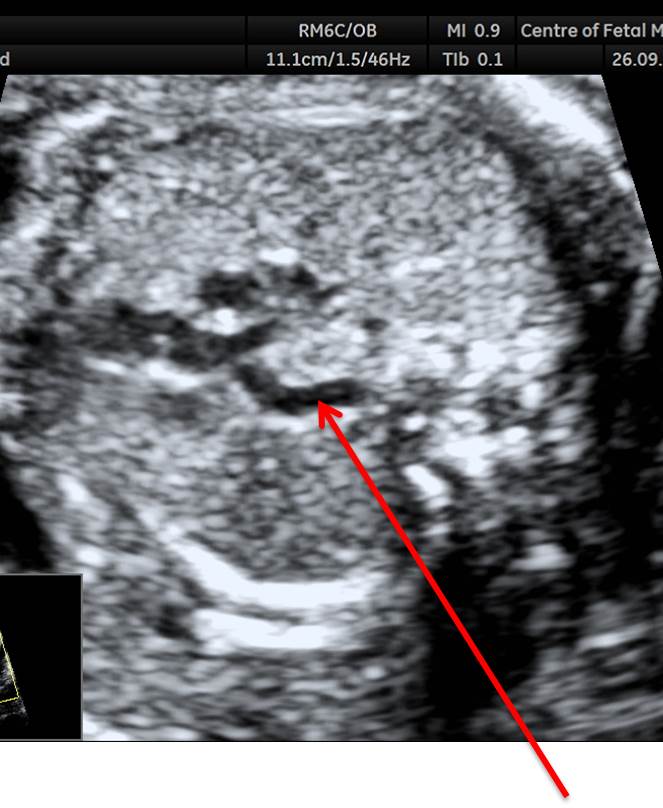

Вопрос 6

1-5.jpg

Какая структура указана стрелкой?

• А — правая легочная артерия;​

• Б — левая легочная артерия;​

• В — правая легочная вена;

• Г — левая легочная вена

Ответ на вопрос 6